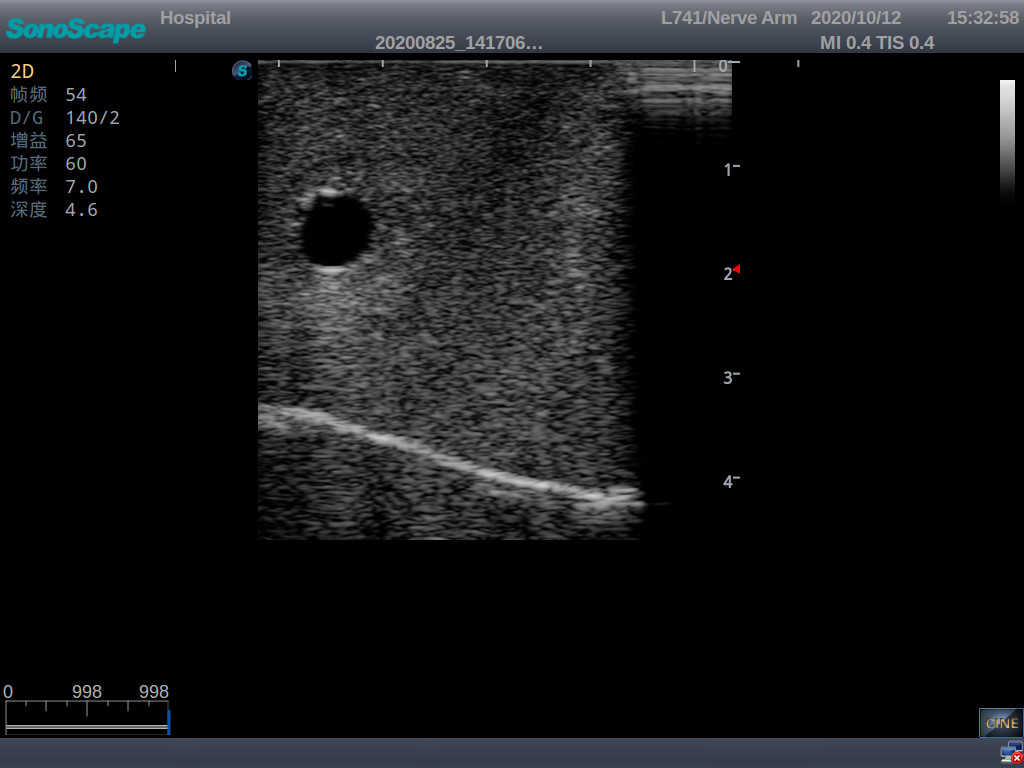

Central Venous Catheterization Ultrasound Training Model

It is a model from the earlobe plane to the umbilical plane with its head turned to one side. It's put in a standard central venipucture and catheterization position, including landmarks such as right arm, clavicle, ribs, sternocleidomastoid muscle, sternoclavicular joint, etc. It can be used for ultrasound-guided subclavian vein and internal jugular vein puncture and catheterization. The model's arm can be used for ultrasound-guided PICC catheter placement.

2)  The puncture module supports using a clinical real ultrasound machine to observe clear images such as right internal jugular vein, right common carotid artery, superior vena cava, right brachiocephalic vein, right brachiocephalic trunk, right subclavian vein, right subclavian artery, etc.

3)  The puncture pad at the arm is made of high-molecular ultrasound material, close to real skin. It can support the use of real ultrasound machines, and the images of tissue structures (skin, subcutaneous tissue, blood vessels) under ultrasound are clear and real